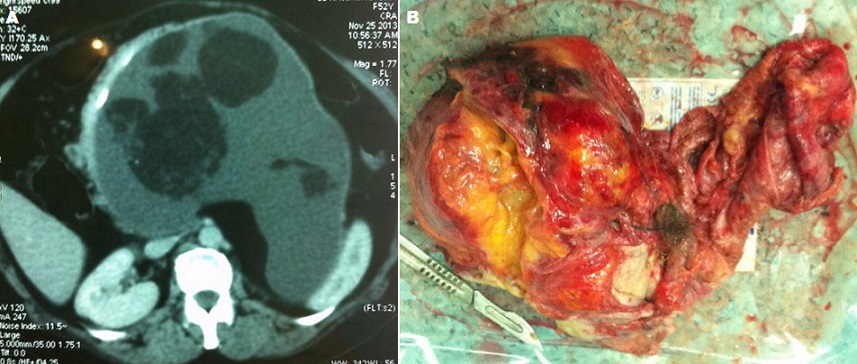

Le tératome rétro péritonéal de l'adulte est une entité très rare, sa découverte tardive s'explique par la pauvreté des signes cliniques et sa localisation rétro péritonéale profonde. Nous rapportons le cas d'une jeune patiente de 40 ans qui a consulté dans notre établissement pour des lombalgies gauches, sensation de pesanteur et une voussure abdominale, l'examen clinique retrouve une patiente en bon état générale une masse solide abdominale occupant l'hypochondre, flanc gauche et l'épigastre. Une échographie abdominale fut réalisé objectivant une masse hétérogène faisant 15 cm de grand axe, un complément scanographique met en évidence une masse rétro-péritonéale hétérogène se rehaussant partiellement après l'injection du produit de contraste et contenant des calcifications (figure 1). devant la gène physique et esthétique rapporté par la patiente une intervention chirurgicale fut programmée et cette masse a été abordé par voie sous costale gauche, après décollement colo-pariétale gauche la masse présente des adhérences avec les structures vasculaires et en essayant d'extirper la masse une blessure de l'artère mésentérique supérieure est observée et malgré sa réparation et sa réimplantation par un greffon de la veine saphène externe, l'état de choc hémorragique n'a pas pu être contrôler malgré les transfusions massives de culots globulaire et l'introduction de drogue vasoactive, le décès de la patiente est survenu 6h après l'intervention. L'aspect macroscopique de la pièce après son exérèse met en évidence une masse solide avec une partie kystique et à son ouverture on a constaté la présence de cartilage osseux ainsi que des cheveux (figure 2). L'étude histologique de la pièce opératoire a mis en évidence un tératome primitif mature.